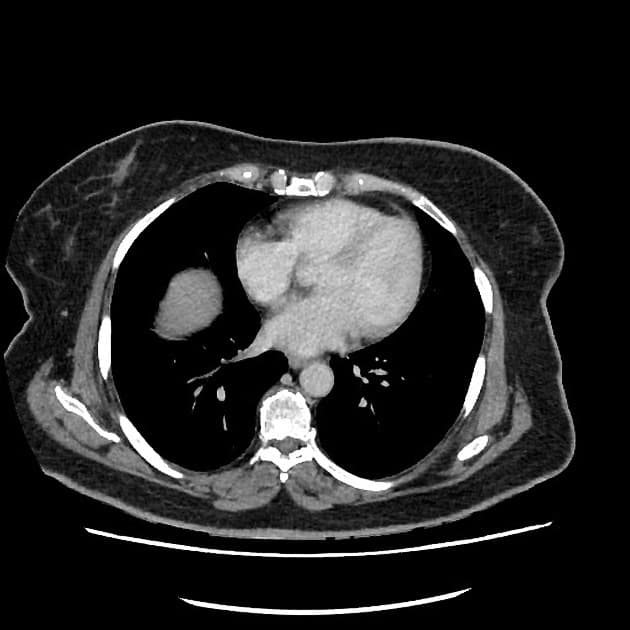

Tụy

Có khối kích thước 3 x 2 cm ở đầu tụy, tăng quang chậm và tiến triển, giảm tăng quang so với phần còn lại của tụy. Ống tụy chính phía trên giãn nhẹ, có hiện tượng tắc đột ngột như thấy trên MRCP gần đây. Không có vôi hóa tụy. Không thấy hình ảnh tắc mật (no evidence of biliary obstruction).

Khối lan xuống dưới vào mạc treo ruột non. Có hẹp nặng khu trú động mạch mạc treo tràng trên (SMV). Tiếp xúc giữa khối và SMV trên đoạn dài 42 mm. Tiếp xúc giữa khối và tĩnh mạch cửa trên đoạn dài 25 mm. Có xâm lấn nhánh tá tràng đầu tiên và thứ hai. Trục tạng, động mạch gan, động mạch mạc treo tràng trên thông thoáng. Động mạch vị tá tràng (GDA) bị bao quanh.

Các nốt nhỏ 4 mm thấy trong mạc treo ruột non. Không có hạch bất thường khác về kích thước hay hình thái ở ổ bụng hay vùng chậu.

Gan có tình trạng xâm nhập mỡ lan tỏa dạng địa lý. Không có di căn gan. Có adenoma tuyến thượng thận trái giàu lipid, kích thước 20 mm. Đây không phải là di căn. Tuyến thượng thận phải bình thường.

Hình ảnh học gợi ý ung thư biểu mô tuyến đầu tụy (pancreatic head adenocarcinoma), về mặt giải phẫu ở mức giới hạn có thể cắt bỏ được do có xâm lấn SMV và các nhánh tá tràng.

Ung thư biểu mô tuyến tụy - có thể cắt bỏ được ở mức giới hạn (borderline resectable)